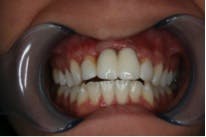

The patient, a 13-year-old female, was seen for emergency treatment in July 2005. The child was catapulted over the handlebars of a bicycle, resulting in the avulsion of the right and left permanent maxillary central incisors. The avulsed teeth were left dry in the palm of her hand for 10 minutes until she reached the hospital where the teeth were placed in milk. Other oral injuries included a laceration on the right side of the philtrum, which was sutured. Examination of the avulsed teeth revealed that the crowns were intact but the mesial incisal edges of both were fractured. Treatment options were explained to the parents and replantation of the avulsed teeth was chosen. She was referred to a local dentist to have the teeth replanted. The roots of the teeth were planed to remove any debris and were then reinserted into the alveolar socket and secured with a splint for six weeks. During the next year the patient had root canals done, followed by metal posts and PFM crowns placed on the avulsed teeth (Figure 1).

Due to the patient’s age at the time of trauma, the crowns were replaced five years later with lava crowns, which are porcelain crowns with a zirconia framework inside (refer to figure 2a and 2b).